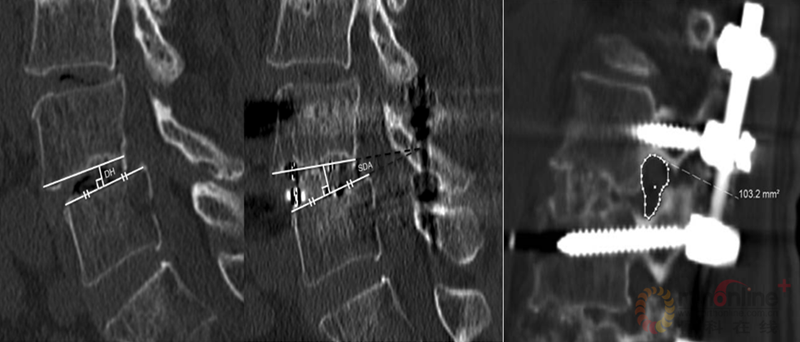

陆军总医院、全军骨科研究所李放教授分析了国内外相关研究,并结合临床经验得出结论:开放手术能够获得更好的矫形和减压效果;微创技术作为脊柱医生手中的新武器,对于一部分畸形较轻的病例,微创技术可以发挥其优势,但要严防特殊并发症;对于畸形严重的病例,微创手术处理存在困难,可谓开放能及微创所不及。他认为,开放和微创技术应该有机结合,重要的是如何去选择适应证,对不同的病例制订个体化方案。